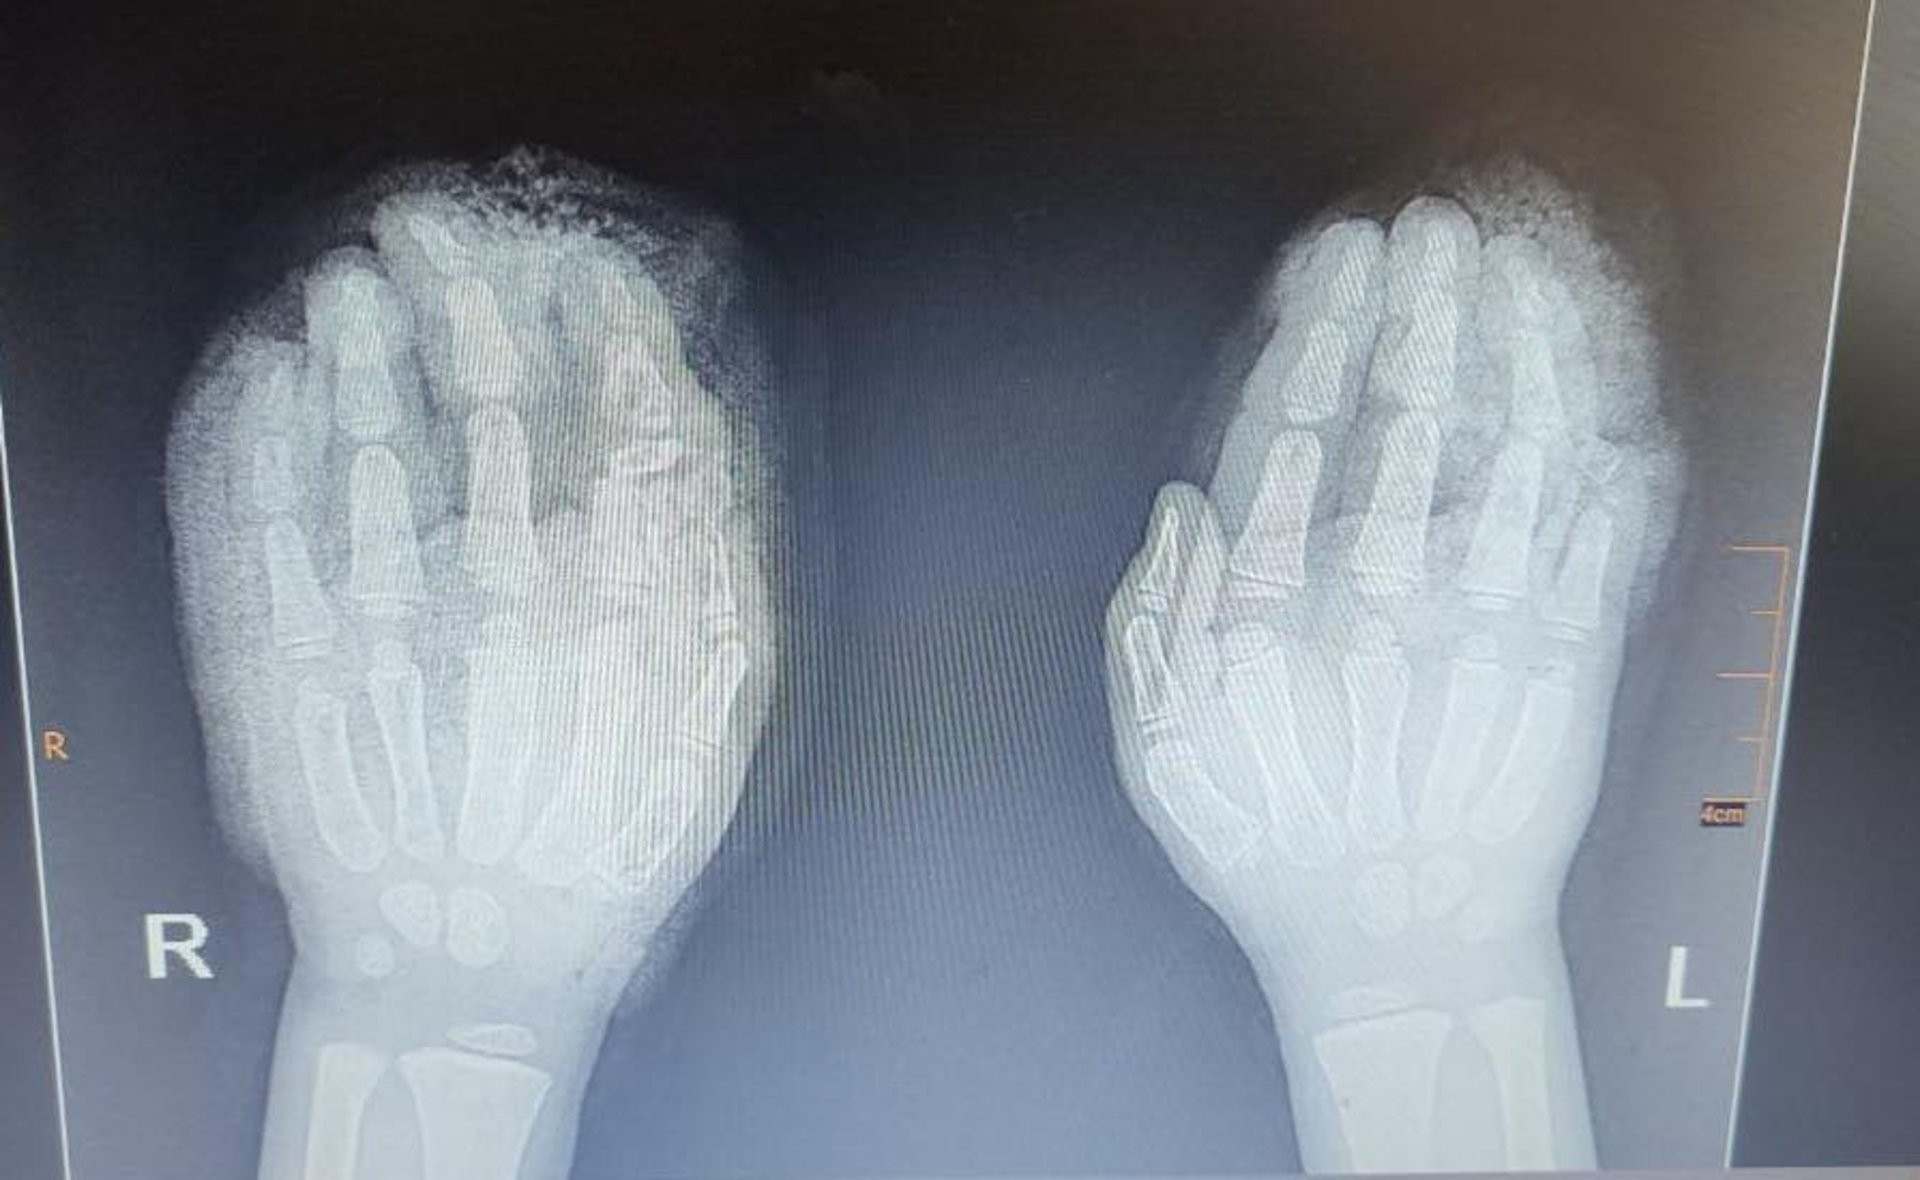

Діагноз при поступленні: множинні рвано-скальповані рани та дефекти шкіри обох кистей, відкриті переломи 2 пальців на правій руці, відкритий перелом 4-го пальця на лівій, часткова втрата м’яких тканин та частини 2-ох пальців.

Команда ортопедів-травматологів у складі Андрія Костюка і Тараса Москаля провела серію складних операцій. Лікарі буквально «збирали» пальці дитини по частинах, уламки пальців були зафіксовані за допомогою спиць. Згодом, коли все зрослось, спиці видалили.

На фото - рентгенівські знімки під час поступлення та фото після багатоетапного хірургічного лікування. А також на фото справа на ліво ортопеди-травматологи: Тарас Москаль та Андрій Костюк.